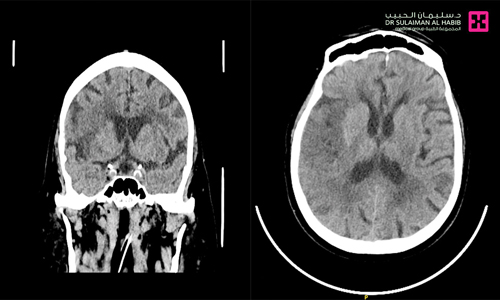

وأضافت أن المريض وصل إلى طوارئ المستشفى عبر الهلال الأحمر بعد ما أصيب بشكل مفاجئ بعدة أعراض حادة في مقدمتها شلل نصفي وصعوبة في النطق إضافة إلى أعراض أخرى أخف وطأة، وقام الفريق الطبي بالطوارئ بتقديم العلاجات الإسعافية اللازمة، ومن ثم أجريت له فحوصات طبية دقيقة، حيث تم عمل أشعة مقطعية للدماغ والشرايين، وأظهرت النتائج وجود انسداد في شريان رئيسي بالدماغ. وبناءً على ذلك تم تفعيل مسار الجلطات الدماغية، واستدعاء الفريق الطبي المختص بالأشعة التداخلية، الذي قام بشكل عاجل باتخاذ كافة الترتيبات المتعلقة بسحب الجلطة الدماغية Mechanical Thrombectomy، وبالفعل أُجريت للمريض عملية عن طريق فتحة صغيرة في شريان الفخذ الأيمن تحت التخدير الكامل، وتم سحب الجلطة بدقة عالية، وإعادة التروية للمنطقة المتأثرة من الدماغ، دون حدوث أي مضاعفات. وقالت د. العيسى إن جهود الفريق الطبي تكلَّلت بالنجاح التام ولله الحمد، ونُقل المريض وهو بحالة مستقرة إلى العناية المركزة للمتابعة لمدة 24 ساعة، قبل أن يتم تحويله إلى غرفة التنويم، وتحسنت حالته الصحية باطراد، حيث تراجعت حدة الأعراض لديه بنسبة تفوق 80 % وغادر المستشفى لاحقاً وهو بحالة صحية جيدة، وبيّنت د. العيسى أن كافة المعطيات الطبية تشير إلى أن حالته ستتحسن أكثر بشكل تدريجي مع برنامج العلاج الطبيعي.